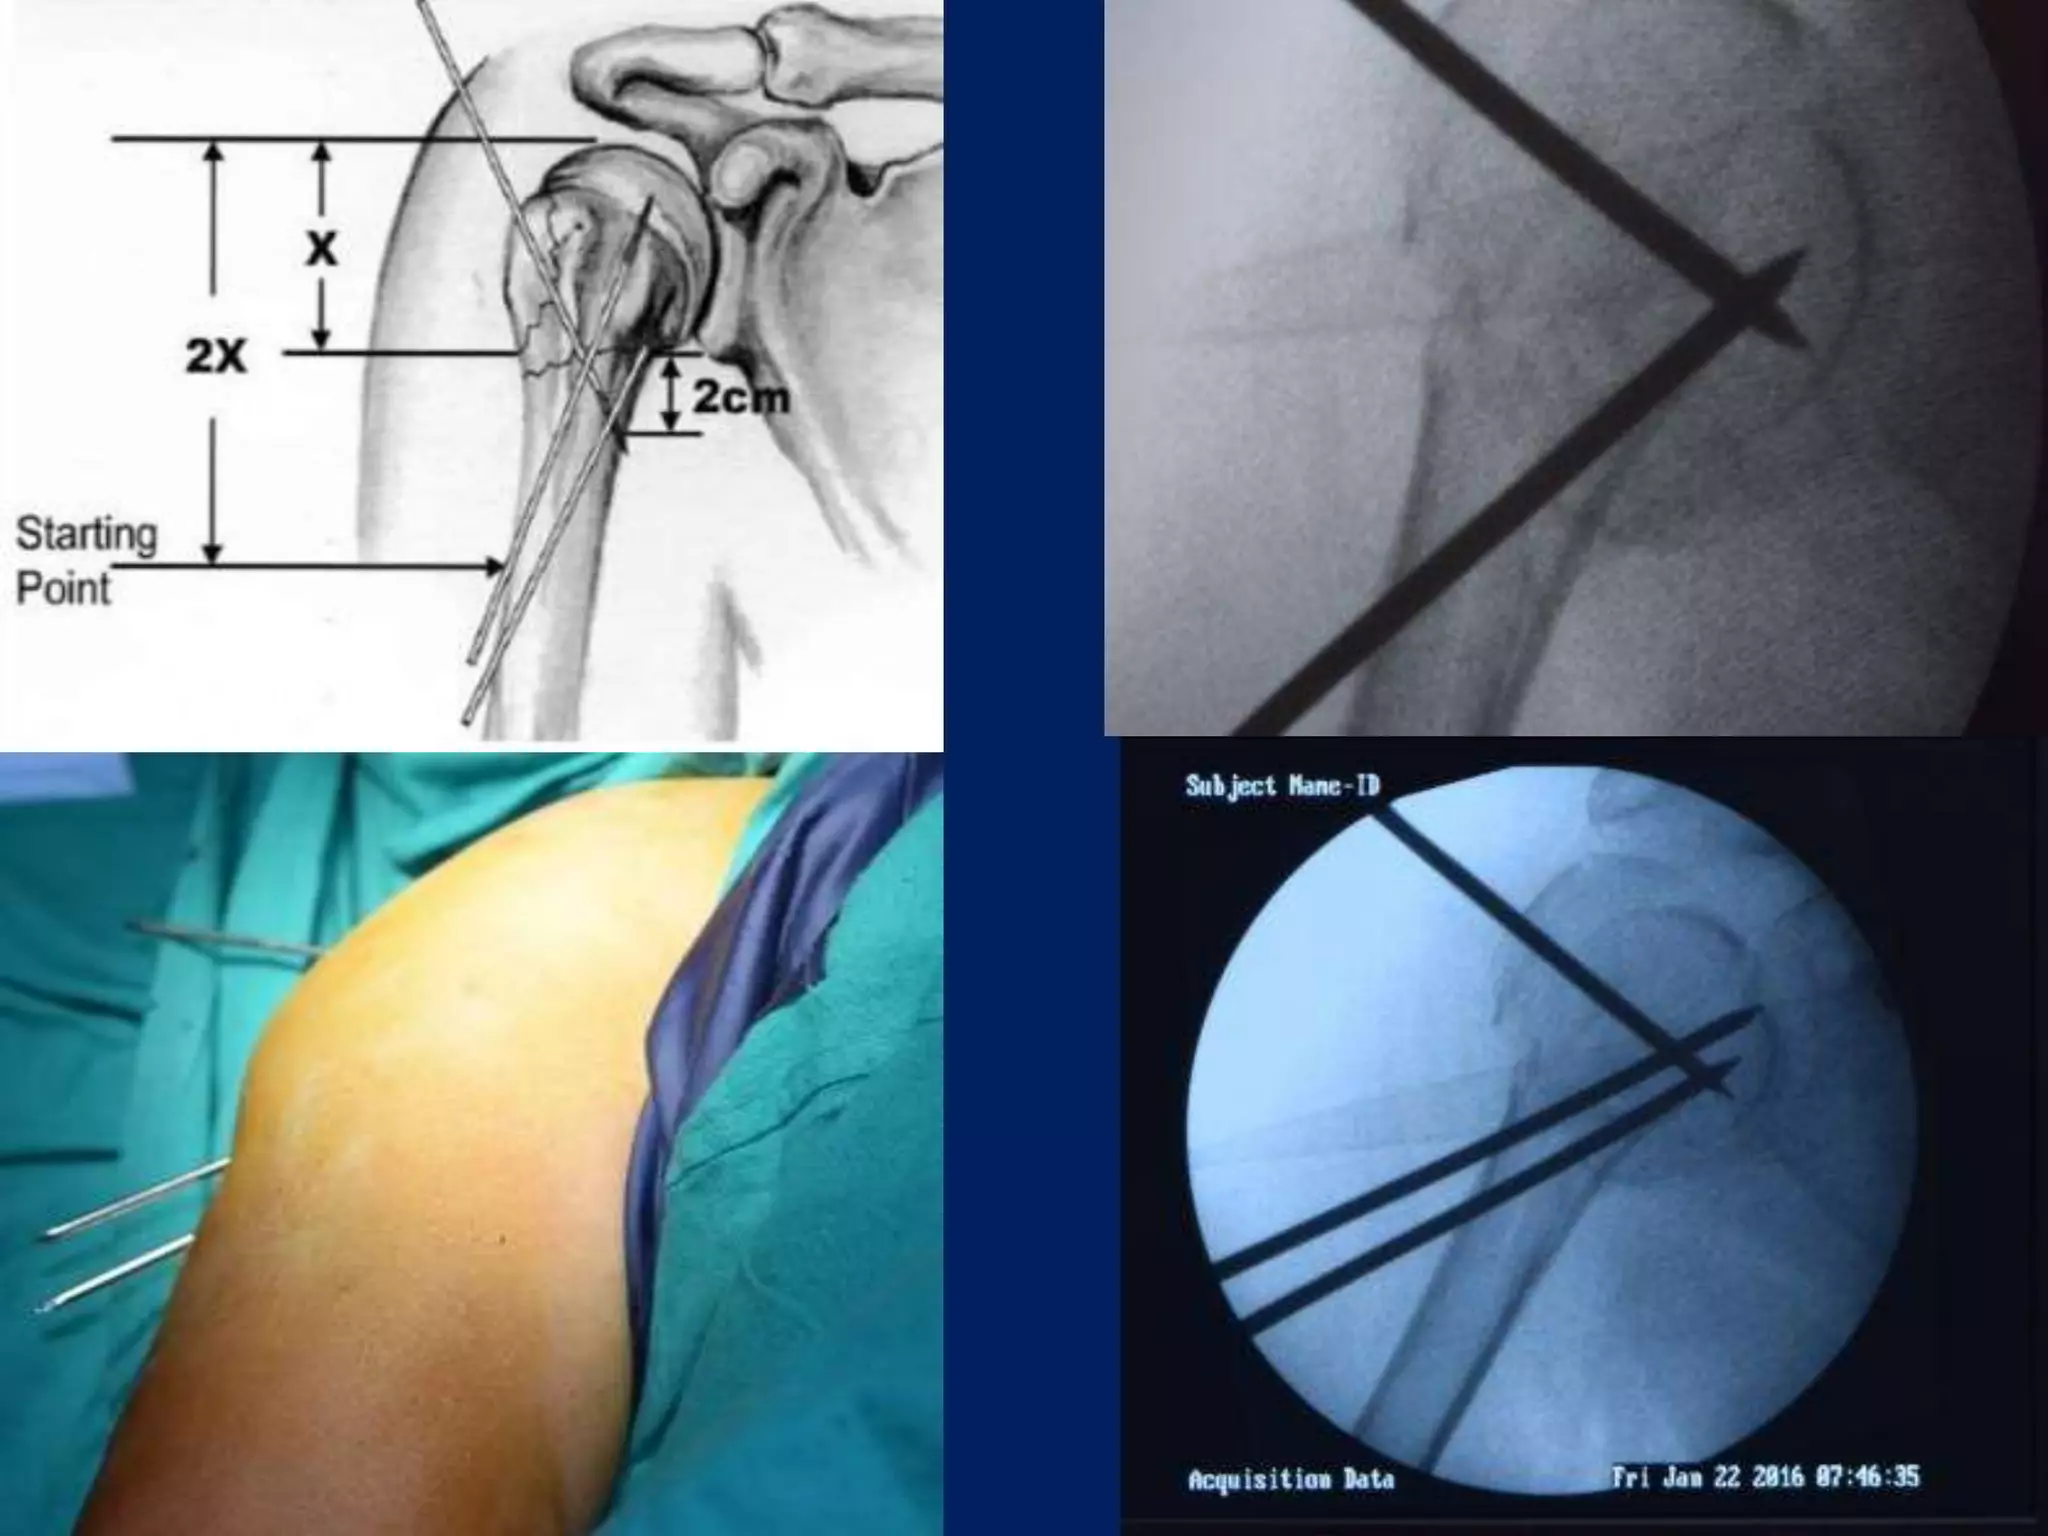

Operative contd... • 2.5mmSchanz pins/ K wire at humeral head at 300 to each other in horizontal plane. • 1st: In true lateral/ coronal plane 2nd: just lateral to bicipital groove 3rd: 300 posterior to 1st one.

• Next 2.5mmpin inserted in coronal plane in line with 1st pin, approximately 4cm or 3 finger/ below the 1st pin in upper third of Humerus. • 3rd pin placed 2cm below the above pin laterally. • Wires are placed from lateral cortex to medial cortex into the head upto the subchondral area

Nabeil Ebraham’s Technique •4 Step technique • 2 pins of 2.5 mm inserted in Shaft. • 2 pins of 2.5 mm in Head. • Head is externally rotated to place Greater tuberosity pin, avoids Axillary nerve, Posterior circumflex humeral artery. • Pins are used as joystick to reduce the fragments external fixator then applied. • Additional anterior pins are added for stability.